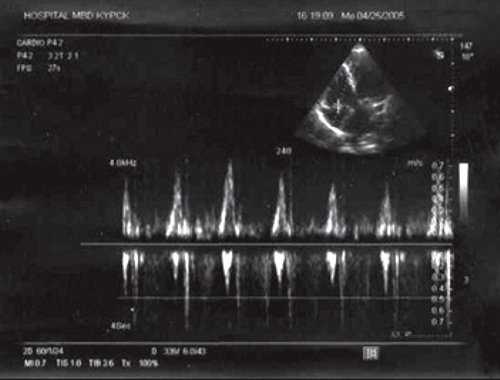

![Трансмитральный поток у больного П ((импульсноволновая допплерография)]()

Рис. 2. Трансмитральный поток у больного П. (импульсноволновая допплерография).

При проведении эхокардиографии в месте обычного расположения левого желудочка лоцировался анатомически правый желудочек, который верифицировался по наличию модераторного пучка. Анатомически правый желудочек соединялся с левым предсердием через трикуспидальный клапан, который лоцировался ближе к верхушке сердца по сравнению с митральным клапаном. Последний соединял морфологически левый желудочек с правым предсердием, в который впадала нижняя полая вена (рис. 1). Определялся параллельный ход магистральных артерий, при этом аорта лоцировалась слева и спереди от легочной артерии. Таким образом, имело место предсердно-желудочковое и желудочково-артериальное несоответствие. У пациента выявлялась также недостаточность митрального и трикуспидального клапанов. На последнем клапане отмечалось увеличение градиента давления (рис. 2, 3).